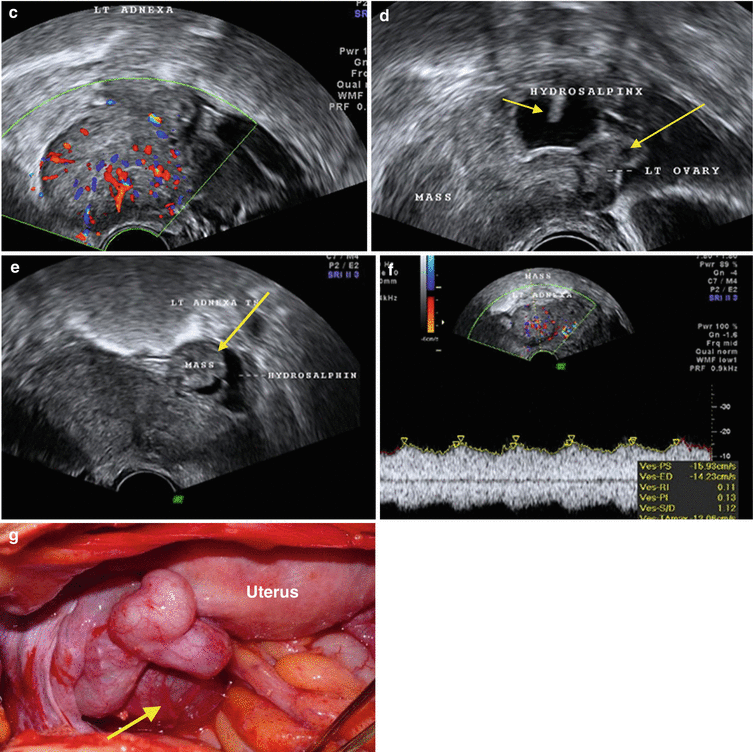

· Bilateral pyosalpinx (a) Greyscale image with right tube showing thick walls with pus within Left adnexal tubal mass showing fluid only in some segments of the tube (b) 3D rendered image showing swollen tubal mucosa and turbid contents,Ovary Patterns, Pearls, and Pitfalls in Adnexal ImagingPelvic congestion syndrome (some prefer pelvic venous insufficiency 9) is a condition that results from retrograde flow through incompetent valves in ovarian veins It is a commonly missed and potentiallytreatable cause of chronic abdominopelvic